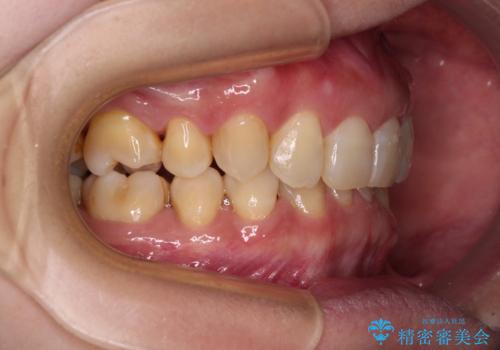

下顎2前歯の欠損 インビザラインによる抜歯矯正

- 下顎前歯欠損による歯列不正を気にして来院された患者様です。

下顎の歯列が小さく、下顎前歯が隠れてしまう過蓋咬合(ディープバイト)であったため、

マウスピースでの抜歯矯正特有の抜歯スペースに向かって奥歯が傾斜する動きが顕著に表れ、ディープバイトは改善されませんでした。

前歯のみが強く接触し、奥歯で咬めない期間も続いたため、ワイヤー装置などを補助的に使用し、何とか終了させることができました。